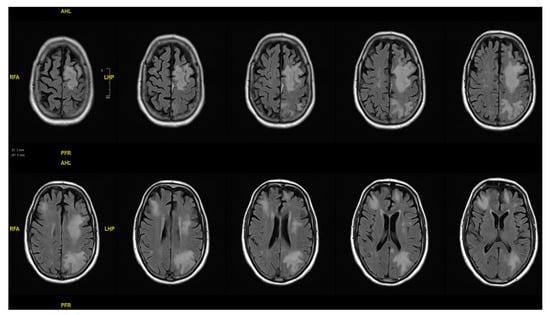

On admission, the patient presented with fluctuating temperatures up to 100.4 °F, confusion, and tested positive for SARS-CoV-2. He was normotensive and well-oxygenated on room air. His initial exam was notable for confusion as well as increased right sided weakness compared to his baseline (residual from spinal cord compression). The patient had received 5 doses of mRNA COVID-19 vaccine, with the last dose administered at least two months prior to symptom onset. He denied experiencing cough, respiratory distress, nausea, vomiting, or diarrhea. He was started on a 3-day course of remdesivir for non-hypoxic COVID-19. On hospitalization day 1, a CT brain scan revealed multiple regions of white matter hypoattenuation, with no evidence of acute infarct or hemorrhage, which were new compared to the last CT scan taken a year before. The Immune Effector Cell-Associated Neurotoxicity Score (ICANS) was 8, losing points for handwriting due to the right-sided weakness. His weakness progressed over the next several days, and on hospital day 3, a brain MRI was performed, showing extensive confluent multifocal sites of T2/FLAIR hyperintense signal abnormalities predominantly in the bilateral frontal lobes and left parietal lobe, along with corresponding restricted diffusion in these areas (Figure 1). By hospital day 4, his progressive weakness had deteriorated, alongside worsening proprioception and vibratory sense in the lower extremities. Following a consultation with the Infectious Disease (ID) team, a lumbar puncture (LP) was performed on hospital day 5, revealing elevated protein levels indicative of nonspecific inflammation. In the CSF analysis, glucose was normal at 54 mg/dL, and protein was elevated at 80, with one RBC and two nucleated cells present. The differential showed 0% polymorphonuclear cells, 68% lymphocytes (within the reference range of 63–99%), and 32% monocytes (within the range of 3–37%). CSF testing for Varicella-Zoster Virus, HSV 1/2, HHV6, and Cytomegalovirus via Polymerase Chain Reaction (PCR) returned negative results. Additionally, VDRL tests in CSF and serum Cryptococcal antigen tests were also negative. No polymorphonuclear leukocytes, no organisms on the Gram stain, and no growth on fungal and mycobacterial cultures were observed. The PCRs for BK virus in the blood and CSF were also negative. Eventually, the JCV PCR test came back positive, leading to a diagnosis of PML.

Figure 1.

Brain MRI axial T2/FLAIR images demonstrating widespread hyperintense white matter abnormalities, predominantly in the frontal and left parietal regions, without signs of recent infarct or hemorrhage.

One limitation of our study is that we cannot entirely exclude immune reconstitution inflammatory syndrome (IRIS) associated with teclistamab immune effects (“unmasking [PML]” IRIS). The consideration of IRIS was prompted by new-onset neurological deficits and multiple cortical hyperintensities in MRI post-teclistamab treatment, typically indicative of an inflammatory response in IRIS [,]. Despite this, the absence of the expected post-contrast enhancement in T2-weighted images, a common indicator of active inflammation in IRIS cases, points towards a reduced likelihood of this IRIS in our patient [] (Figure 1). Additionally, the lack of immunoglobulin-level data precludes us from determining whether the patient had hypogammaglobulinemia, which could influence both his susceptibility to infections and his inflammatory response. This uncertainty also makes it unclear whether treatment with IVIG could have conferred any benefit if it was given, further complicating our understanding of the immune dynamics in this case.